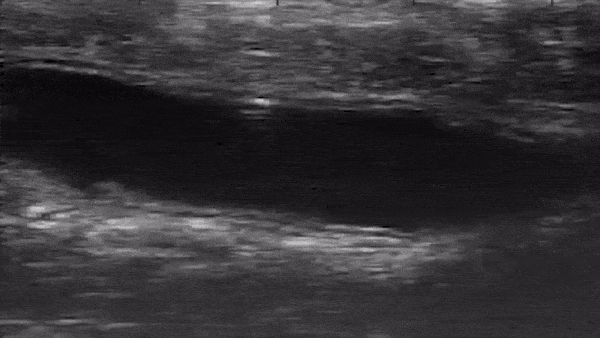

Grundsätzlich ist der Ansatz so simpel wie brillant: Mikroroboter, die innerhalb eines menschlichen Organismus implementiert werden, könnten dort wichtige Aufgaben übernehmen. So wäre es denkbar, auf diese Weise Medikamente und andere Wirkstoffe gezielt an die richtige Stelle zu transportieren. Auch bei Untersuchungen – etwa Darmspiegelungen – oder sogar bei der Bekämpfung von Krebszellen könnten die kleinen Roboter zum Einsatz kommen. Doch die Praxis hinkt der Theorie noch deutlich hinterher. Denn bisher existieren solche Mikroroboter nur im Labor und auf dem Papier. Nun aber scheint Forschern an der amerikanischen Purdue University ein entscheidender Durchbruch gelungen zu sein: Sie implementierten einen solchen Mikroroboter im Darm einer Maus. Erstmals konnte die Technologie so in einem lebendem Organismus getestet werden. Bild: Purdue University video/Elizabeth Niedert and Chenghao Bi Der Roboter wird durch ein rotierendes Magnetfeld angetrieben Zuvor allerdings waren einige Vorbereitungen nötig. So musste der Darm geleert, mit Salzlösung gefüllt und durch Atropin ruhiggestellt werden. Anschließend führten die Wissenschaftler den nur 800 mal 400 mal 100 Mikrometer großen Roboter in das Organ des Tieres ein. Ein rotierendes Magnetfeld sorgte daraufhin dafür, dass sich die Konstruktion um ihre eigene Querachse drehte. Auf diese Weise bewegte sich der Roboter wie ein kleines Rad durch den Darm der Maus. Übermäßig große Geschwindigkeiten wurden dabei nicht erreicht. So maßen die Forscher ein Tempo von 2 mm/s. Dies bringt aber auch Vorteile mit sich. Denn die vergleichsweise langsamen Begegnungen stellen sicher, dass die Darmwände unbeschädigt bleiben. Es steht also nicht zu befürchten, dass der Einsatz der Roboter letztlich mehr Schaden anrichtet als nutzt. Auch deshalb sollen nun weitere Experimente folgen. Die Position kann mithilfe von Ultraschall bestimmt werden Die Forscher lösten zudem ein schon seit längerer Zeit bestehendes Problem. Denn die Mikroroboter sind so klein, dass sie keine eigene Energieversorgung besitzen können. Folgerichtig können sie auch keine Daten übermitteln oder die eigene Position bestimmen. Möchte man die Position des Roboters von außerhalb des Körpers bestimmen, kann dies mithilfe von Röntgenstrahlen geschehen. Ein solches Vorgehen wäre allerdings extrem aufwändig. Die Forscher in den Vereinigten Staaten setzten daher auf hochfrequenten Ultraschall. Dieser ermöglichte es, die Bewegungen des Mikroroboters zu beobachten. Noch müssen die Wissenschaftler aber herausfinden, wie sie ihre Konstruktion am besten steuern können. Langfristig wäre es dann denkbar, mit den kleinen Robotern gezielt gegen kranke Zellen vorzugehen und so Tumore zu bekämpfen. Via: Purdue University Teile den Artikel oder unterstütze uns mit einer Spende. Facebook Facebook Twitter Twitter WhatsApp WhatsApp Email E-Mail Newsletter